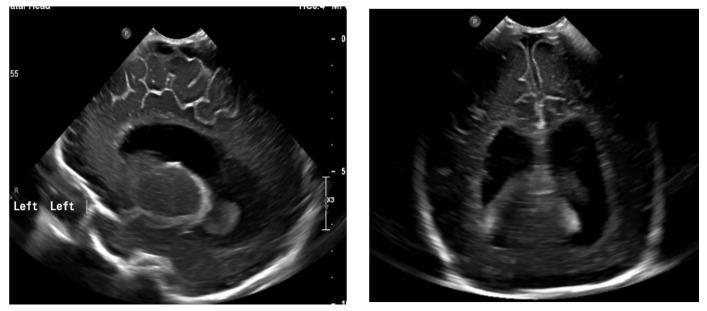

Spina bifida aperta (SBA), with (myelomeningocele) or without (myeloschisis) a hernia sack, is the most common congenital defect of the central nervous system. Prenatal surgical closure of SBA lowers the risk for developing shunt-dependent hydrocephalus, which offers a chance at improved motor, urinary, and gastrointestinal function. A total of 96 patients who had undergone open surgery prenatal repair for SBA were analyzed. The patients were divided into two groups: Group I-12 patients (12.5%)-without a hernia sack (myeloschisis) and Group II-84 patients (87.5%)-with a hernia sack (myelomeningocele). In this study, we demonstrated that prenatal SBA repair was statistically significantly less often associated with the need for ventriculoperitoneal shunting ( > 0.00001). The shunting was statistically significantly more often required in patients from Group I ( > 0.004). The absence of a hernia sack increases the risk for developing shunt-dependent hydrocephalus in patients after prenatal SBA repair. However, as prenatal SBA repair is associated with better motor, urinary, and gastrointestinal function, increased risk of developing shunt-dependent hydrocephalus in fetuses without a hernia sack should not be treated as a contraindication to prenatal intervention.

开放性脊柱裂(SBA),伴有(脊髓脊膜膨出)或不伴有(脊髓裂)疝囊,是最常见的中枢神经系统先天性缺陷。产前手术闭合SBA可降低发生依赖分流的脑积水的风险,这为改善运动、泌尿和胃肠功能提供了机会。对96例接受开放性产前手术修复SBA的患者进行了分析。患者分为两组:第一组-12例患者(12.5%)-无疝囊(脊髓裂),第二组-84例患者(87.5%)-有疝囊(脊髓脊膜膨出)。在本研究中,我们证明产前SBA修复与脑室腹腔分流术需求的相关性在统计学上显著降低(>0.00001)。第一组患者在统计学上更常需要进行分流术(>0.004)。无疝囊会增加产前SBA修复术后患者发生依赖分流的脑积水的风险。然而,由于产前SBA修复与更好的运动、泌尿和胃肠功能相关,无疝囊胎儿发生依赖分流的脑积水风险增加不应被视为产前干预的禁忌证。